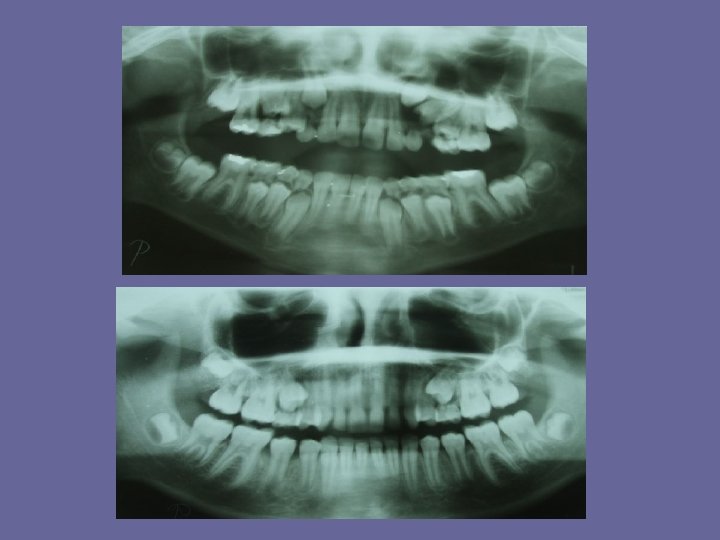

REPLACEMENT OF INCISORS The average difference in wide of the deciduous and permanent incisors is 7 mm in maxilla and 5, 5 mm in mandible. Space for these teeth, which are larger then their deciduous predecessors (particularly the uppers), is provided by: 1. utilization of existing spacing between the deciduous incisors 2. an increase in arch width takes place during the eruption of incisors. The amount of it is about 3, 5 mm in maxilla and 2, 0 mm in mandible. 3. an increase of length of dental arches, 2, 5 mm in maxilla and 2, 0 mm in mandible. 4. the permanent incisors are more proclined and thus form a larger arch than the deciduous incisors.

REPLACEMENT OF INCISORS

REPLACEMENT OF INCISORS While the lower primate spacings are important to allow arrangement of the first permanent molars in right relationship, the uppers provide the space for upper permanent incisors.

REPLACEMENT OF INCISORS • the deciduous dentitions without spacings (primate and between incisors) are liable to be replaced by crowded permanent dentition.